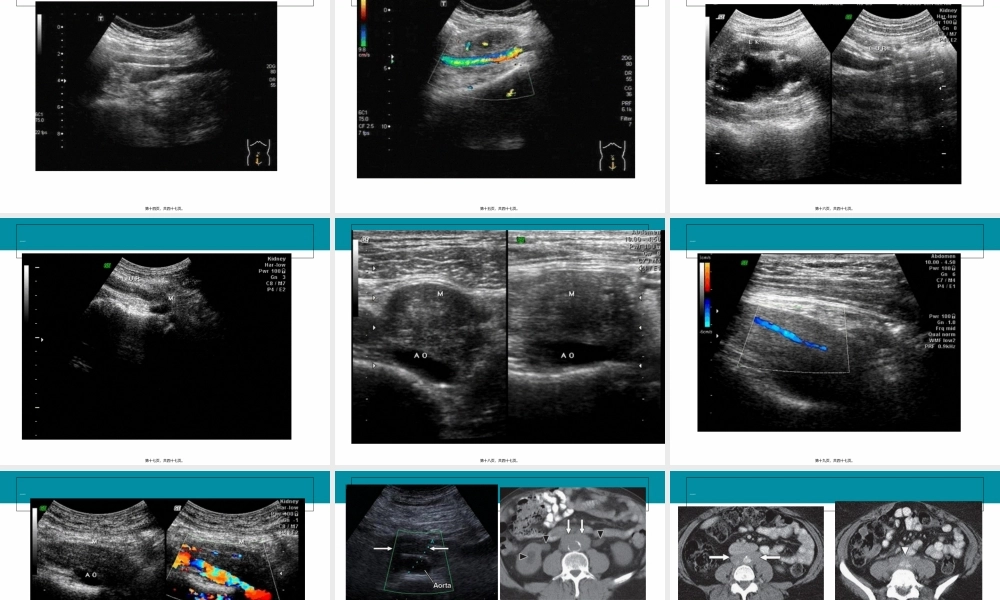

腹膜(fùmó)后纤维化ClicktoaddText第一页,共四十七页。概述(àishù)ɡ•腹膜后纤维化(RPF)是一种少见的,原因(yuányīn)不明的以腹膜后纤维化为特点的非特异性化脓性炎症(胶原性的腹膜后血管炎症)•1.特发性,可能与自身免疫反应或过敏性疾病有关。•2.继发性,腹主动脉瘤等因素有关,较多见。可能与恶性肿瘤,外伤和手术,药物,炎症,放射线治疗。第二页,共四十七页。ClicktoaddTitle•法国泌尿科医生Albarran于1905年首先发现输尿管梗阻可继发于腹膜后的纤维化改变;1948年Ormond经过对两个病例的详细描述确立其为一种独立的疾病;该病先前曾被称为慢性织脉周炎、输尿管周围炎、硬化型腹膜后肉芽肿;输尿管梗阻是腹膜后纤维化最常见的合并症,排泄性尿路造影或逆行肾盂(shènyú)造影可用于检查梗阻的位置及梗阻的程度第三页,共四十七页。病理(bìnglǐ)表现•病理表现为灰白色的纤维(xiānwéi)斑块,境界不清,包绕侵犯周围脏器,其中包括对输尿管及下腔静脉的侵犯;•显微镜下证实存在成纤维细胞伴有大量炎性细胞浸润,主要有淋巴细胞、巨噬细胞、血管内皮细胞,其中很多是人类白细胞DR抗原(HLA-DR)组织学上表现为不同程度的炎性反应,由不同成熟度的纤维化组织构成,早期主要为多灶性脂肪变性坏死,淋巴细胞,单核细胞,嗜酸性粒细胞和异物巨噬细胞浸润。中期炎性细胞减少,有较多的成纤维细胞出现,毛细血管增生和胶原纤维形成,由于增生的毛细血管内皮连接不紧密,大量液体,蛋白质及红细胞可进入血管外间隙。后期炎性细胞,新生血管,成纤维细胞消失,肉芽肿形成并机化,形成大量致密纤维硬化组织,水含量减少。斑块由外侧向中线逐渐成熟。•第四页,共四十七页。ClicktoaddTitle•特发性通常发生于肾门水平至髂动脉分叉的腹主动脉周围,常伴有明显的主动脉粥样硬化。病变累及输尿管可致其狭窄,进而引起肾盂(shènyú),输尿管积水为本病的特征,严重者可伸延者腹腔内的组织和器官。第五页,共四十七页。流行病学(liúxínbìnxué)ɡɡ•RPF的发病率约二十万分之一,大多发生于40—60岁的中老年人,男女发病率之比约2-3:1;无种族差异;约70%为特发性的,约30%为继发性的,与炎症、腹膜后恶性肿瘤及药物(yàowù)等有关,罕见的儿童及家族性发病的报告也曾被报道过。第六页,共四十七页。ClicktoaddTitle•多数学者认为RPF是一种免疫系统疾病,与多种免疫介导结缔组织疾病有关,因此建议使用免疫抑制剂治疗。•假设RPF是晚...